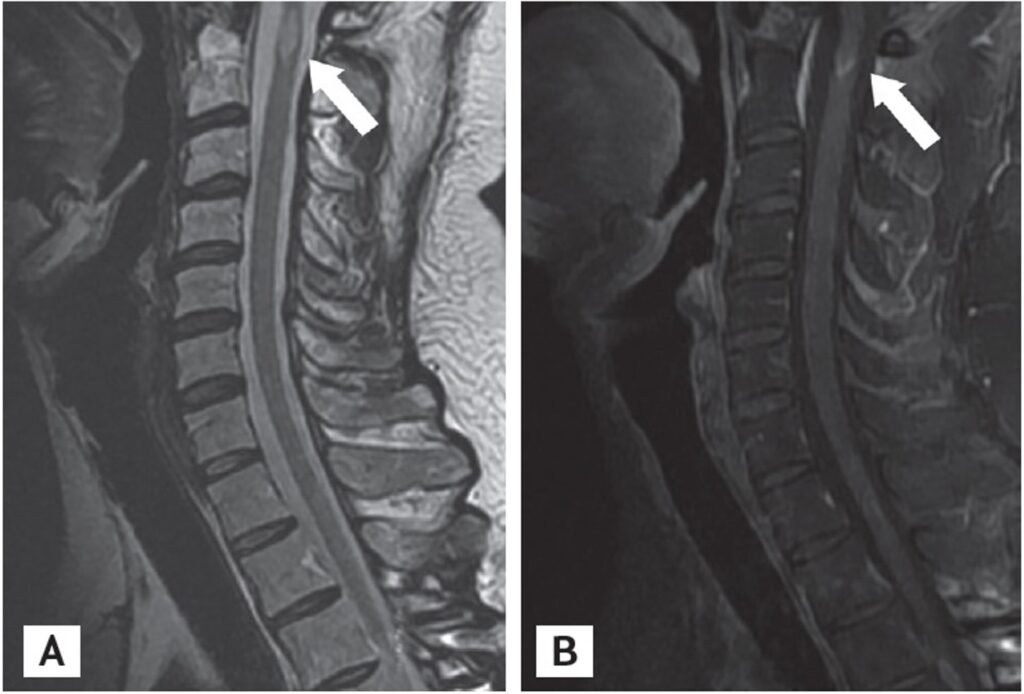

Intradural Lesions with a diagnosis of Transverse Myelitis. T2 hyperintensity lesion T8-T12 in a 20–24-year old participant who presented with progressive paraplegia over 3 weeks. A diagnosis of transverse myelitis was made and the patient improved on steroids.

Magnetic resonance imaging (MRI) scans of the spine and brain. (A, B) Sagittal T2-weighted MRI of the thoracic cord demonstrates an intramedullary enhancing lesion at T3 (arrows). (C, D) Axial T2-weighted MRI of the brain shows round hyperintense lesions with slight enhancement in the right temporal subcortex (arrowheads).

Magnetic resonance imaging (MRI) scans of the cervical spine (secondary bilateral lower leg weakness 3 years after allogeneic stem cell transplantation). (A, B) Sagittal T2-weighted MRI of the cervical cord demonstrates an intramedullary enhancing lesions at C1 and C2 (arrows). The previous enhancing lesion (at T3) disappeared.